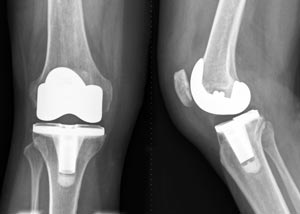

Knee replacement surgery — also known as knee arthroplasty (ARTH-row-plas-tee) — can help relieve pain and restore function in severely diseased knee joints. During knee replacement, a surgeon cuts away damaged bone and cartilage from your thighbone, shinbone and kneecap and replaces it with an artificial joint made of metal alloys, high-grade plastics and polymers.

Knee replacement surgery (arthroplasty) involves replacing a damaged, worn or diseased knee with an artificial joint.

1. total knee replacement (TKR) – both sides of your knee joint are replaced